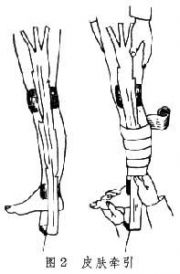

| 2021年7月26日 (一) 20:01 | 皮肤牵引.jpg (文件) |  |

12 KB | 77921020 | Uploaded with SimpleBatchUpload | 3 |